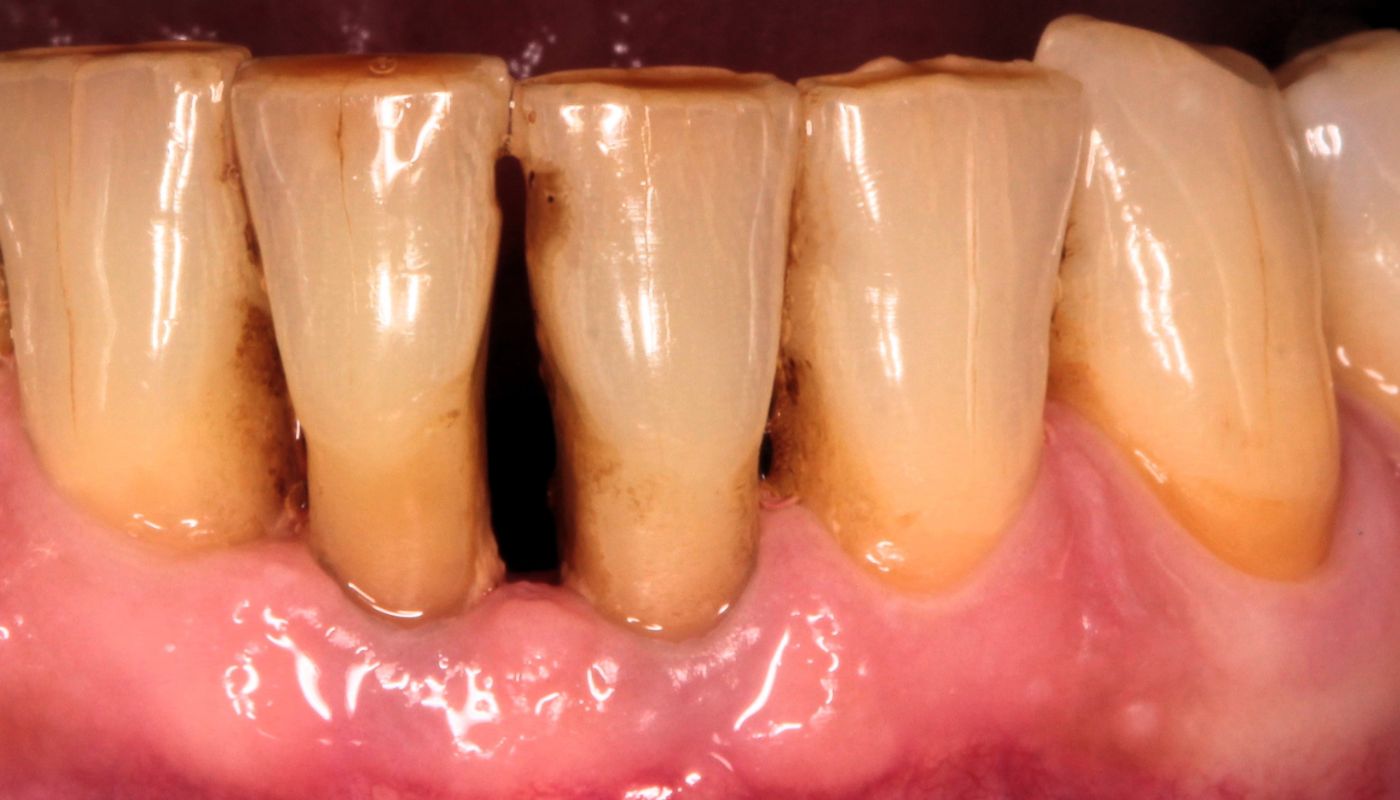

Odsłonięcie szyjek zębowych, gdzie pojawia się stan zapalny, spowodowane jest nagromadzeniem się płytki bakteryjnej, która doprowadza do powstawania kamienia nazębnego. Nieleczona wiele lat choroba przyzębia, zwana paradontozą (z łac.periodontitis) powoduje trwałe zanikanie dziąseł i kości, a w konsekwencji odsłonięte szyjki oraz powierzchnie korzeni.

Niewłaściwa higiena zębów czy palenie papierosów stwarzają idealne warunki narastania płytki nazębnej na powierzchni zębów. Zalegające złogi nazębne stykając się z dziąsłami powodują ich drażnienie, przez co stwarzają podłoże do wytwarzania stanu zapalnego przyzębia. Dochodzi do obniżania się nasady zęba oraz odsłaniania szyjek zębowych.

Najczęściej popełnianym błędem przez pacjentów jest rezygnowanie z mycia zębów czy stosowania nici dentystycznej, w momencie kiedy pojawi się krwawienie dziąseł. Pojawienie się krwi już przy delikatnym oczyszczaniu zębów powinno być dla każdego pacjenta lampką ostrzegawczą, że należy poprawić higienę jamy ustnej.

Bagatelizowanie tego stanu nie tylko powoduje postępowanie problemu odsłoniętych szyjek zębowych, ale również nieleczone przez długi czas może doprowadzić do ruchomości, a nawet utraty zębów.